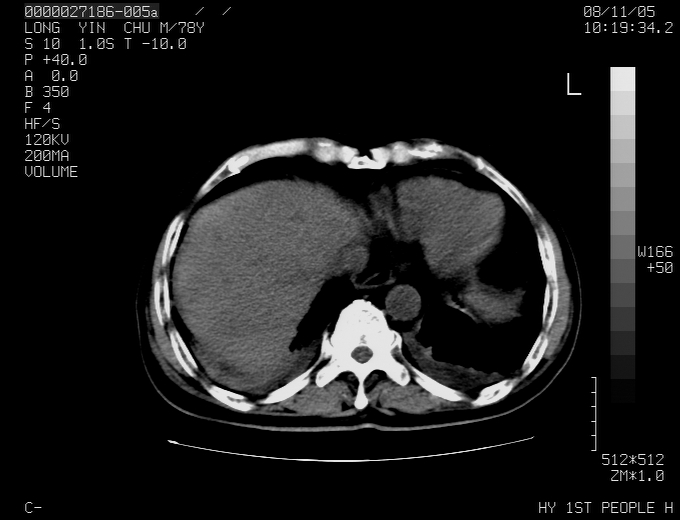

标题: CT16532:M78Y,肝脏病变,请会诊

腹胀,腹痛就诊,男性,78岁,外院b超未见异常。

肝ca,脾肾转移

考虑弥漫性肝癌并脾及双肾转移.双侧胸水.

图片质量欠佳:多考虑:左侧肾癌。脾脏转移!胸膜转移!

肝脾肾转移瘤可能性大,左肾不除外梗塞,双侧胸水